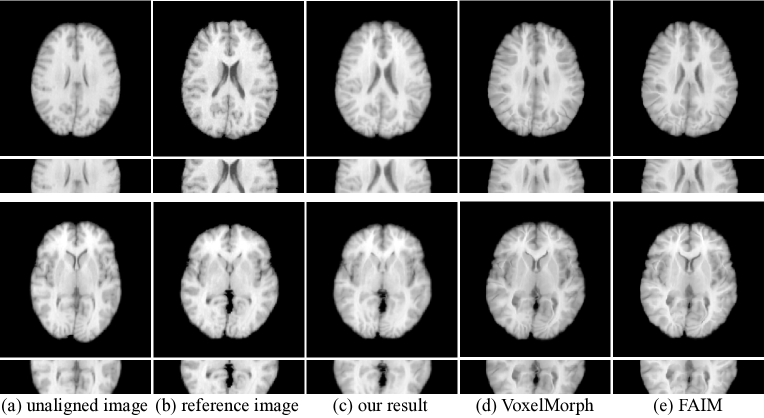

Figure 3: Visual comparison of the results produced by our method and other methods.

Figure 3 presents the visual comparison results produced by different registration methods. From the results, we can see that other methods tend to fail to the match the shape of the reference image or lose the structure details while our method is able to produce the result that is more consistent with the reference image and better preserves the internal structures.